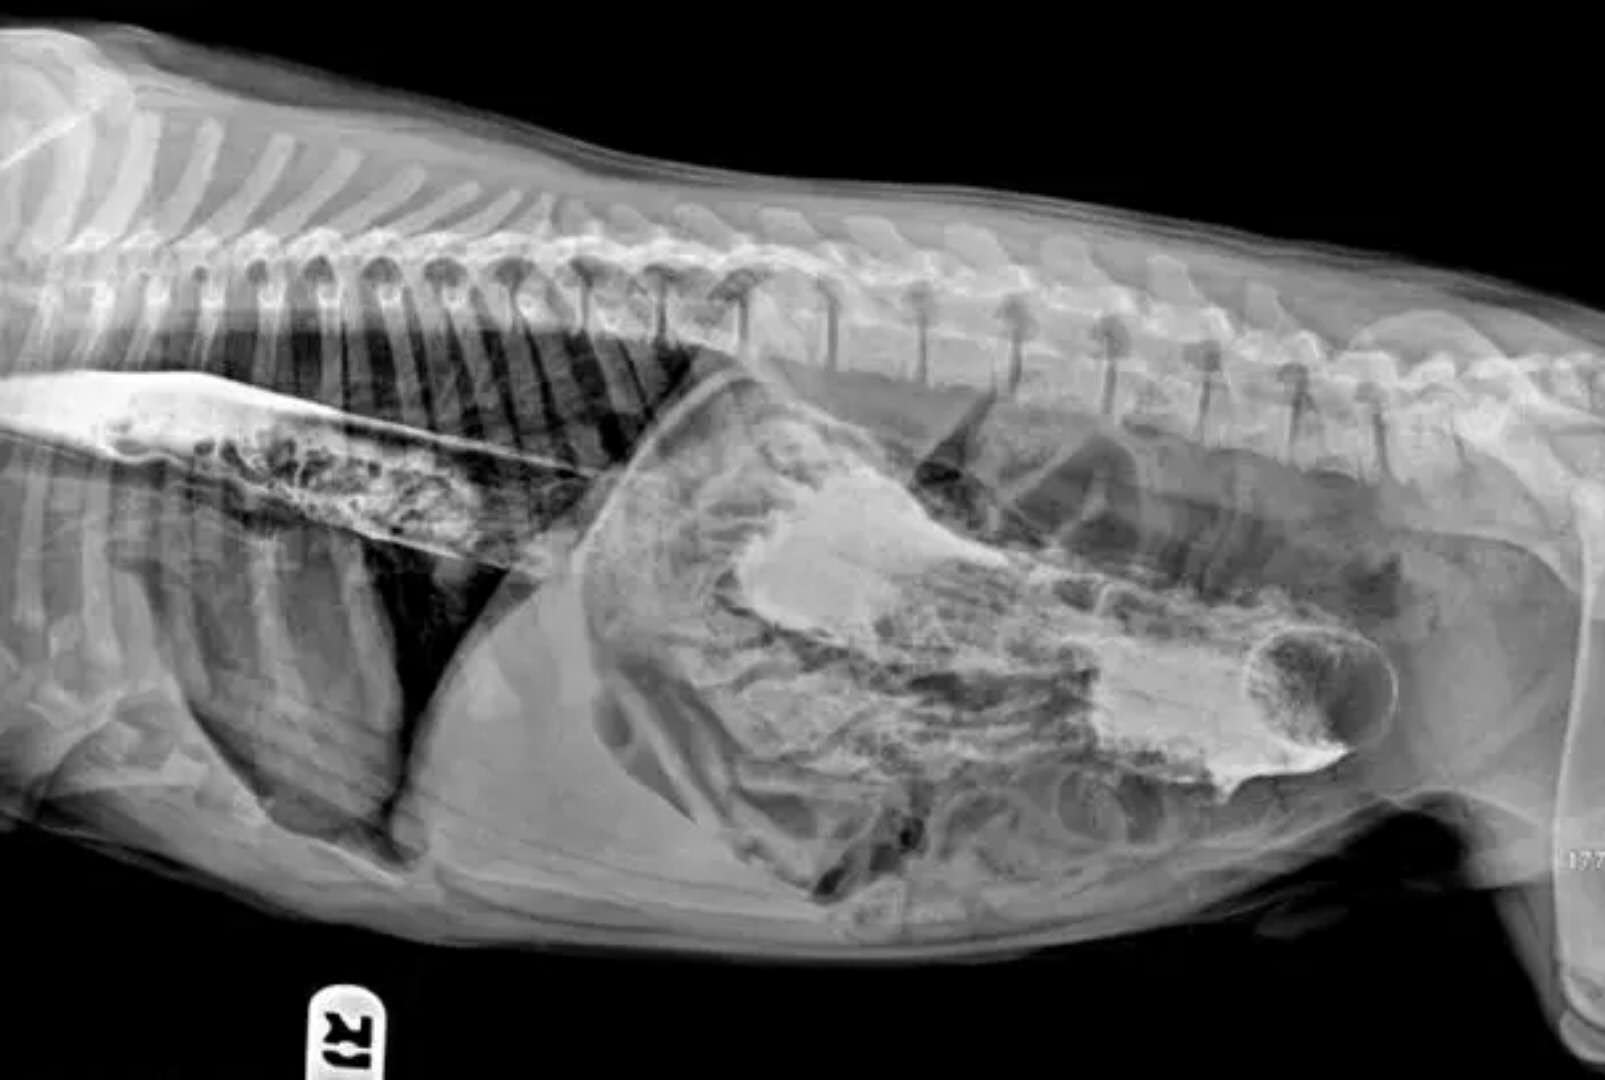

这是小孩的玩具车

这些都是在狗狗的胃里发现的,拍的X光图,看到那把刀在狗狗胃里,心里不紧张吗不担心 ,万一你家的狗狗也吃下去,想都不敢想!

狗狗似乎总是无法控制自己去吃一些没有营养价值的东西。针线、木勺、硬果壳、果核、塑料袋、珠宝、石块、抹布和袜子都有可能吃下去,狗狗胃内长期滞留这些异物不能被胃液消化,会造成胃黏膜损伤,影响胃功能。